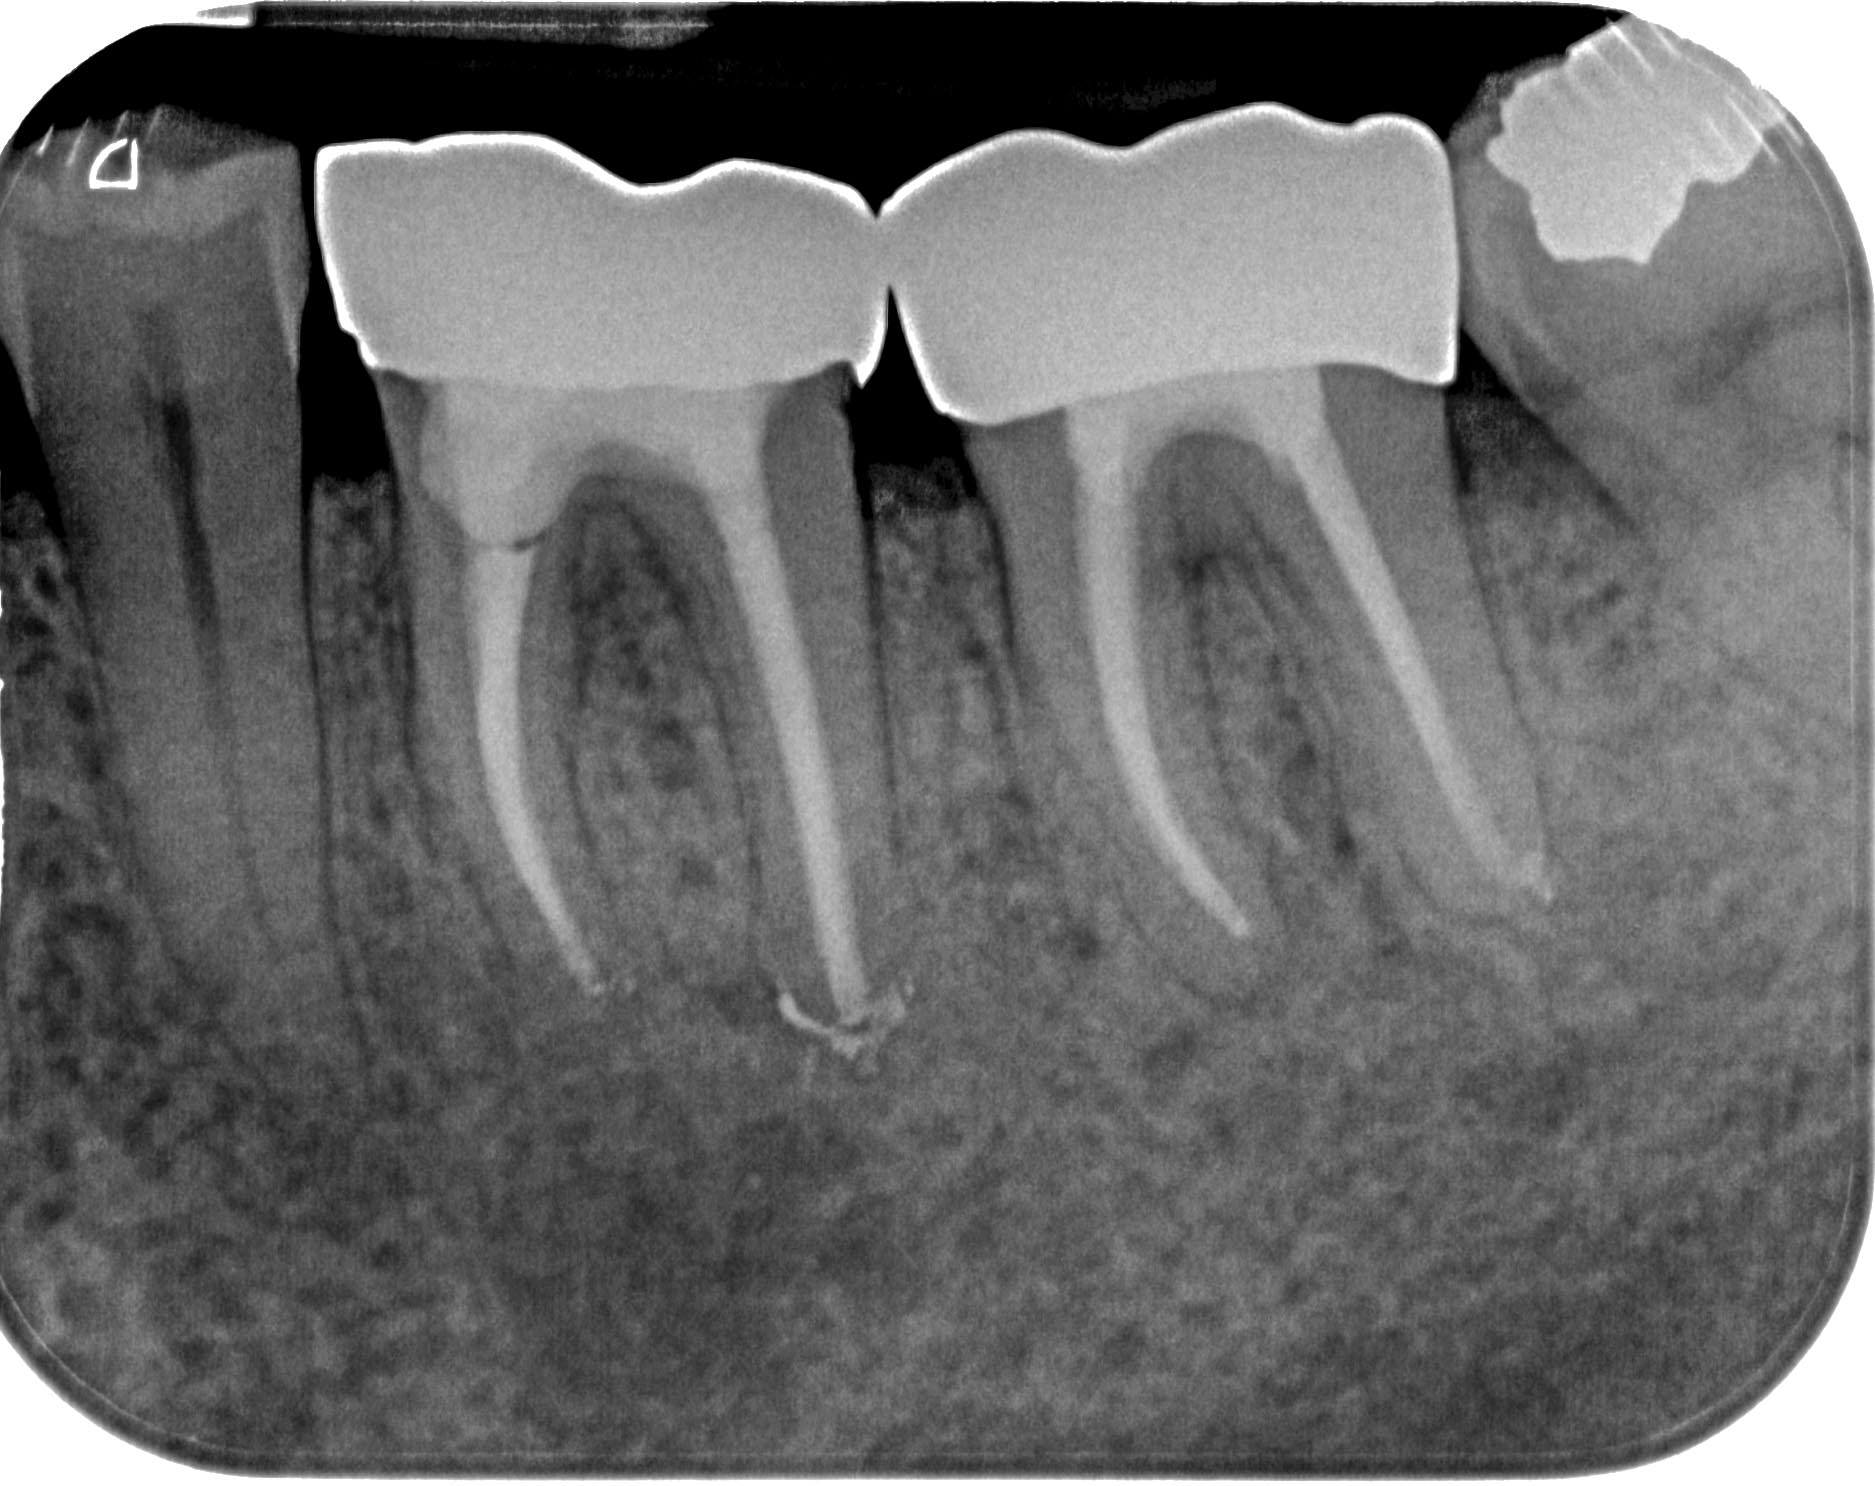

mt3637-3

3 Haselnüsse (1)